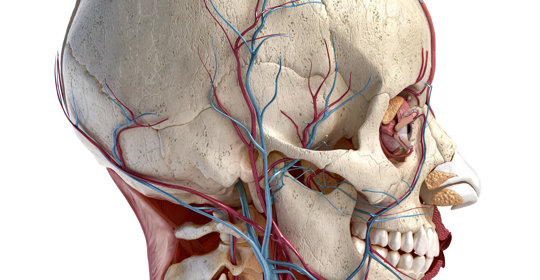

顱神經損害:不同型別的症狀與診斷

顱神經損害:頭痛、暈眩、視力異常、步履不穩及噁心

顱神經損害:三叉神經痛、第六腦神經麻痺

顱神經損害:舌下神經功能及損傷後果